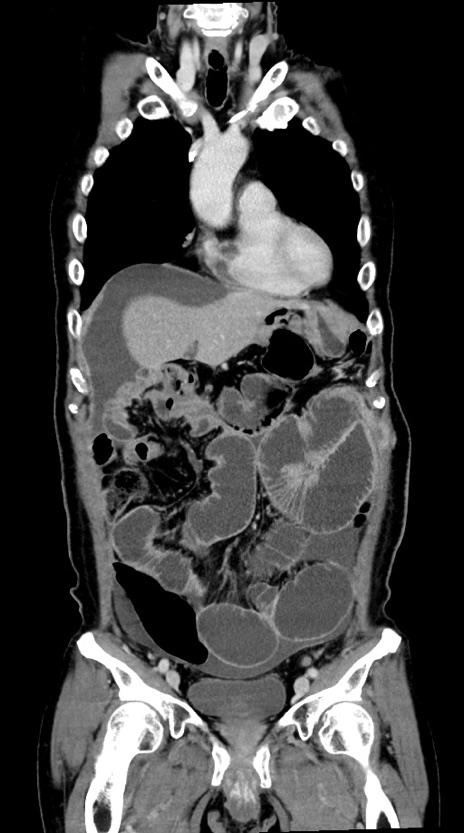

横断像

【症例】60歳代男性

【主訴】嘔吐

【現病歴】胃癌にて胃全摘後。食思不振が悪化し、夜中に嘔吐することがある。

【既往歴】胃癌、胃全摘、脾摘、胆摘後

【データ】WBC 5900、CRP 10.56